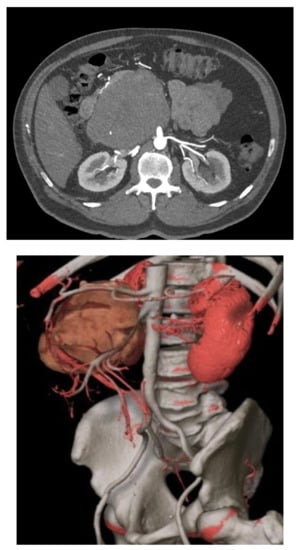

Vascular resections can be partial or complete. The type of reconstruction, if any, will be determined by the type of vessel, extent of the tumor infiltration, and patency of vessel at the time of resection. Venous resections can be partial (side-wall resection) as they have greater compliance than arteries due to their thinner smooth muscle layer. Partial venous resections can be performed with a vascular stapler or can be performed sharply with subsequent closure of venotomy with primarily suture venorraphy or a patch using a biologic (e.g., bovine pericardium) or synthetic graft to avoid critical venous narrowing after the tumor has been resected (Figure 3).

Figure 3. IVC partial resection with patch repair.